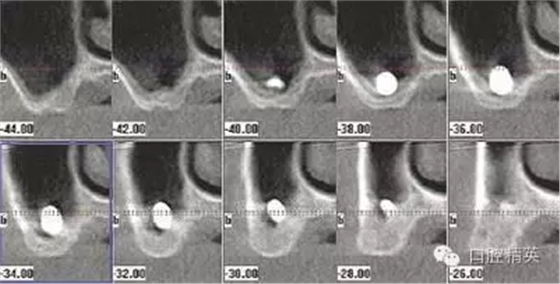

圖1a:術(shù)后根尖片顯示種植體傳入左側(cè)上頜竇

圖1b:術(shù)后ICAT三維CBCT從另外一個角度顯示種植體穿入左側(cè)上頜竇的情況

我們通過文獻(xiàn)和網(wǎng)站檢索獲得了一些關(guān)于種植體失敗的研究和綜述文章。一個和僅使用兩維放射診斷(根尖片或曲斷片)有關(guān)的常見失敗是上頜竇穿孔。(圖1a-c)通常牙醫(yī)由于錯誤的估計了上頜竇底骨量高度而造成幾個毫米的上頜竇底穿孔。一些病例可能沒有癥狀,象圖中所示的這個病例,患者需要嚴(yán)格的監(jiān)控、復(fù)查。有些病例則出現(xiàn)并發(fā)癥,種植體不得不取出。